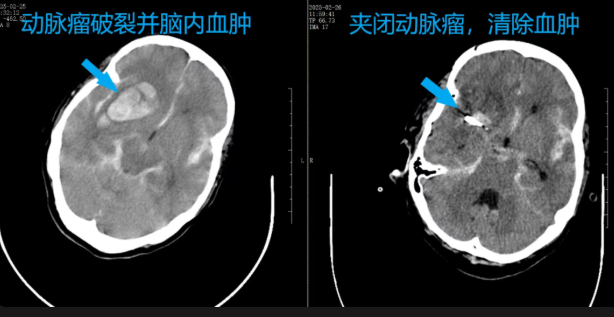

2025 年 2 月 25 日深夜,王姨在家中突發(fā)不省人事,送至粵西醫(yī)院時已陷入深度昏迷。經(jīng)過頭顱 CTA 檢查快速明確關(guān)鍵病情:右側(cè)大腦中動脈瘤破裂、右側(cè)顳葉大量出血,左側(cè)后交通動脈瘤,患者已出現(xiàn)腦疝先兆,隨時可能導(dǎo)致呼吸循環(huán)衰竭。

常駐電白的廣東省人民醫(yī)院神經(jīng)外科專家毛承亮教授帶領(lǐng)團隊分析病情:患者左右腦各有一個動脈瘤,考慮右腦的大腦中動脈瘤為此次出血的“元兇”。在沒法兩側(cè)兼顧的情況下,“先做右側(cè)開顱,夾閉破裂的動脈瘤并清除顱內(nèi)血腫,挽救生命!左腦未破裂動脈瘤待病情穩(wěn)定后再行微創(chuàng)介入治療!”毛教授立即為王姨制定了最佳的個體化治療方案。

2 月 26 日凌晨 2 時,手術(shù)正式開始。毛承亮教授帶領(lǐng)粵西醫(yī)院神經(jīng)外科團隊(梁海波主任醫(yī)師等),在顯微鏡下精準夾閉破裂的動脈瘤,同時清除了腦內(nèi)的血腫。凌晨5時,手術(shù)順利完成,患者轉(zhuǎn)入重癥醫(yī)學(xué)科監(jiān)護。并終于在兩周后蘇醒、轉(zhuǎn)出ICU病房。